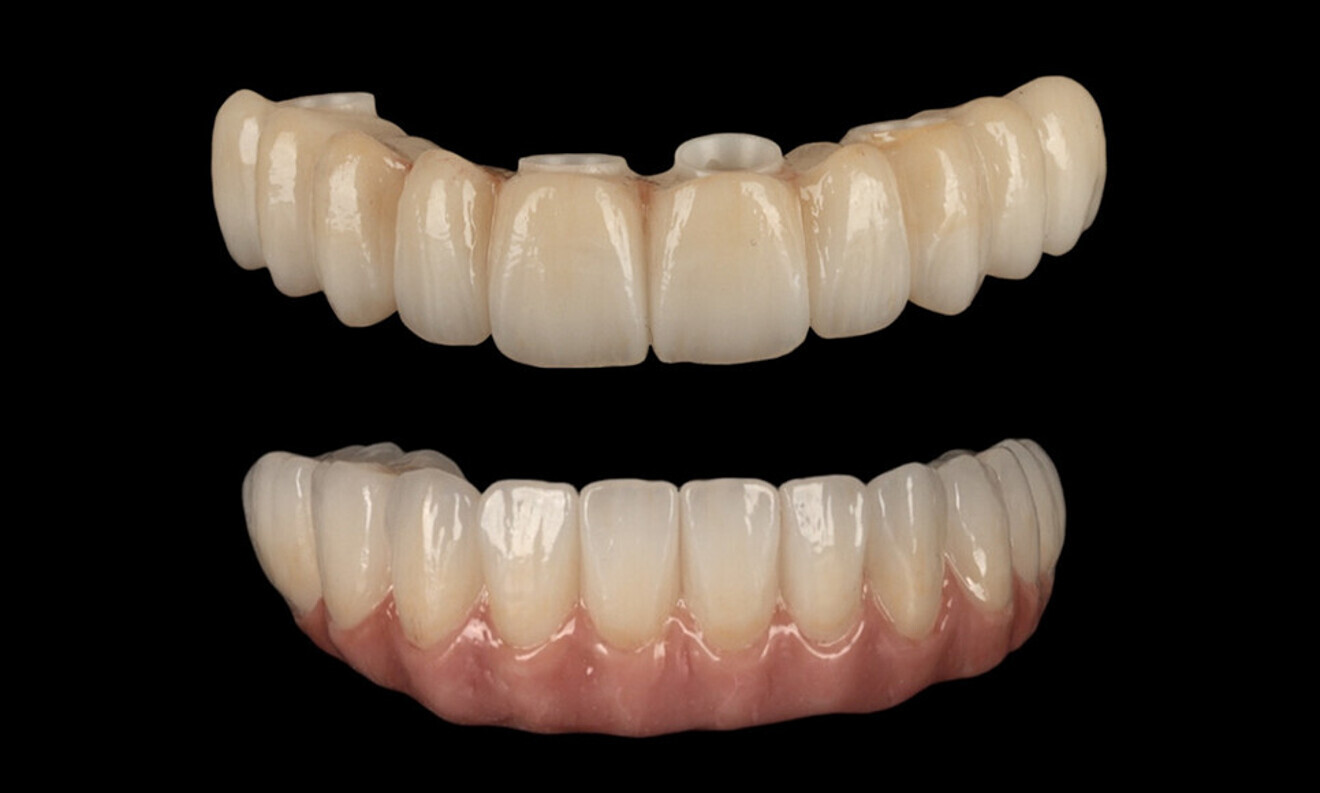

After a healing period of five months and successful osseointegration, the process for the definitive restorations was initiated. The chosen material was milled monolithic zirconia, and Variobase final abutments was used, placed on the screw-retained abutments to ensure excellent stability and retention of the definitive restorations (Figs. 69–75).

Figs. 69–75: The definitive restorations were fabricated after a five-month healing period

The soft tissue was in good condition, and the definitive restorations were placed (Figs. 76 & 77). After placing the definitive restorations, oral hygiene instructions were given to ensure proper care and prevent complications. Additionally, the occlusion was carefully checked and adjusted as needed (Figs. 78–83).